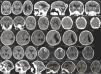

Table 1 summarizes clinical and radiological findings. It was possible to access head computer tomography (CT) scans of 95 infants confirmed with microcephaly and 21 discarded cases. Some radiological findings are presented in Fig. 3. CT scans revealed intracranial calcifications in 78/95 (82.1%) confirmed microcephaly cases and in 1/25 (4.8%) of discarded cases (p<0.001). Among confirmed cases with calcifications, two children had calcifications on basal nuclei (not shown). Ten (10.5%) confirmed cases presented lissencephaly-pachygyria spectrum alterations, 7 (7.4%) presented hydrocephalus, and 5 (5.3%) presented agenesis of the corpus callosum. In addition, 40 infants underwent transfontanelar ultrasound (US) (20 confirmed and 20 discarded cases). Among infants with confirmed microcephaly, 11 (55%) presented dilated cerebral ventricles and 3 (15%) presented a sonographic diagnosis of hydrocephalus. Transfontanelar US detected 6 (30%) children with calcifications.

Head computer tomography scans of confirmed microcephaly cases in the state of Piauí, Brazil, 2015–2016.

(A) Calcifications at the interface between white and gray matter and in the core-capsular regions. Moderate ventricular ectasia associated with parallelism of the lateral ventricles, suggesting dysgenesis of the corpus callosum. Deformity of the skull and volume reduction of the cerebellum due to atrophy, with enlargement of the cerebrospinal fluid space of the posterior fossa.

(B) Small calcifications at the interface between white and gray matter. Scarcity of cortical sulci, configuring an alteration of the spectrum of lissencephaly.

(C) Small calcifications at the interface between white and gray matter, linear and punctiform. Scarcity of cortical sulci, configuring an alteration of the spectrum of lissencephaly.

(D) Small calcifications at the interface between white and gray substances, linear and punctiform. Asymmetry of the cerebral hemispheres with accentuation of the cortical sulci and volumetric reduction of the left hemisphere due to atrophy, with consequent compensatory ectasia of the lateral ventricle.

(E) Slight parallelism of the lateral ventricles, suggesting dysgenesis of the corpus callosum.

(F) Small punctate calcifications at the interface between white and gray matter, and gross calcification in the left frontal lobe. Scarcity of cortical sulci with few shallow sulci, configuring an alteration of the spectrum of lissencephaly. Slight parallelism of the lateral ventricles, suggesting dysgenesis of the corpus callosum. Deformity of the skull in high frontal region.

(G) Small punctate calcifications at the interface between white and gray matter and periventricular region. Scarcity of cortical sulci, configuring an alteration of the spectrum of lissencephaly. Volumetric reduction of the cerebellum. Deformity of the skull.

(H) Small punctate calcifications at the interface between white and gray matter in the right frontal lobe. Scarcity of cortical sulci, in addition to shallow sulci, configuring an alteration of the spectrum of lissencephaly. Expansion of the extra-axial fluidic spaces, more evident in the temporal fossae. Reduction of right hemisphere volume with compensatory ectasia of the right lateral ventricle.

In this series, 87 newborns were submitted to ophthalmologic evaluation (67 confirmed cases and 20 discarded cases). The most frequent fundoscopic findings in confirmed cases were retinal pigment epithelium rarefaction (9/67 [13.4%]), retinal pigment epithelial atrophy (6/67 [9%]), and papillary pallor (3/67 [4.8%]). All examinations of discarded cases were normal. With the objective of neonatal screening for deafness, RRCM evaluated otoacoustic emissions in 91 newborns in the first week of life (70 confirmed and 21 discarded cases). The frequency of absence of otoacoustic emissions was 21/70 (30%) among the confirmed cases and 2/21 (9.5%) among the discarded cases (p=0.051).